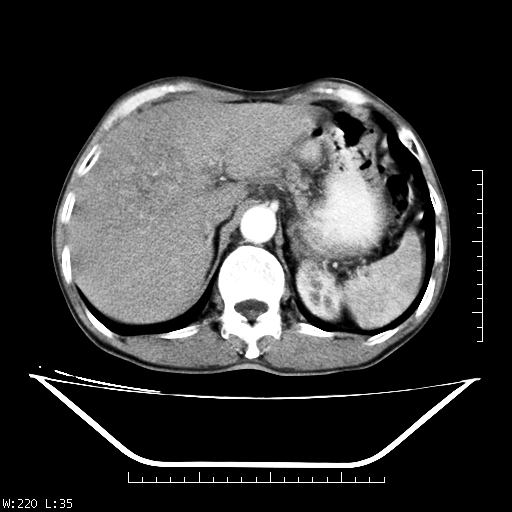

男,70,右上腹痛两月,有乙肝病史,b超提示肝占位,ct如下,请会诊。

肝右叶类圆型密度减低影,密度不均,边界清晰其内可见更低密度影,腹膜后可见小淋巴结肿大,增强扫描动脉期病灶明显强化,静脉期及延时扫描见强化不明显,快进快出表现。

平扫呈低密度占位,动脉期斑片状明显强化,病灶边缘清晰,见假包膜;门脉期呈低密度,符合肝癌快进快出强化特征

1.肝右叶低密度影考虑为肝癌;

2.肝转移待除外。